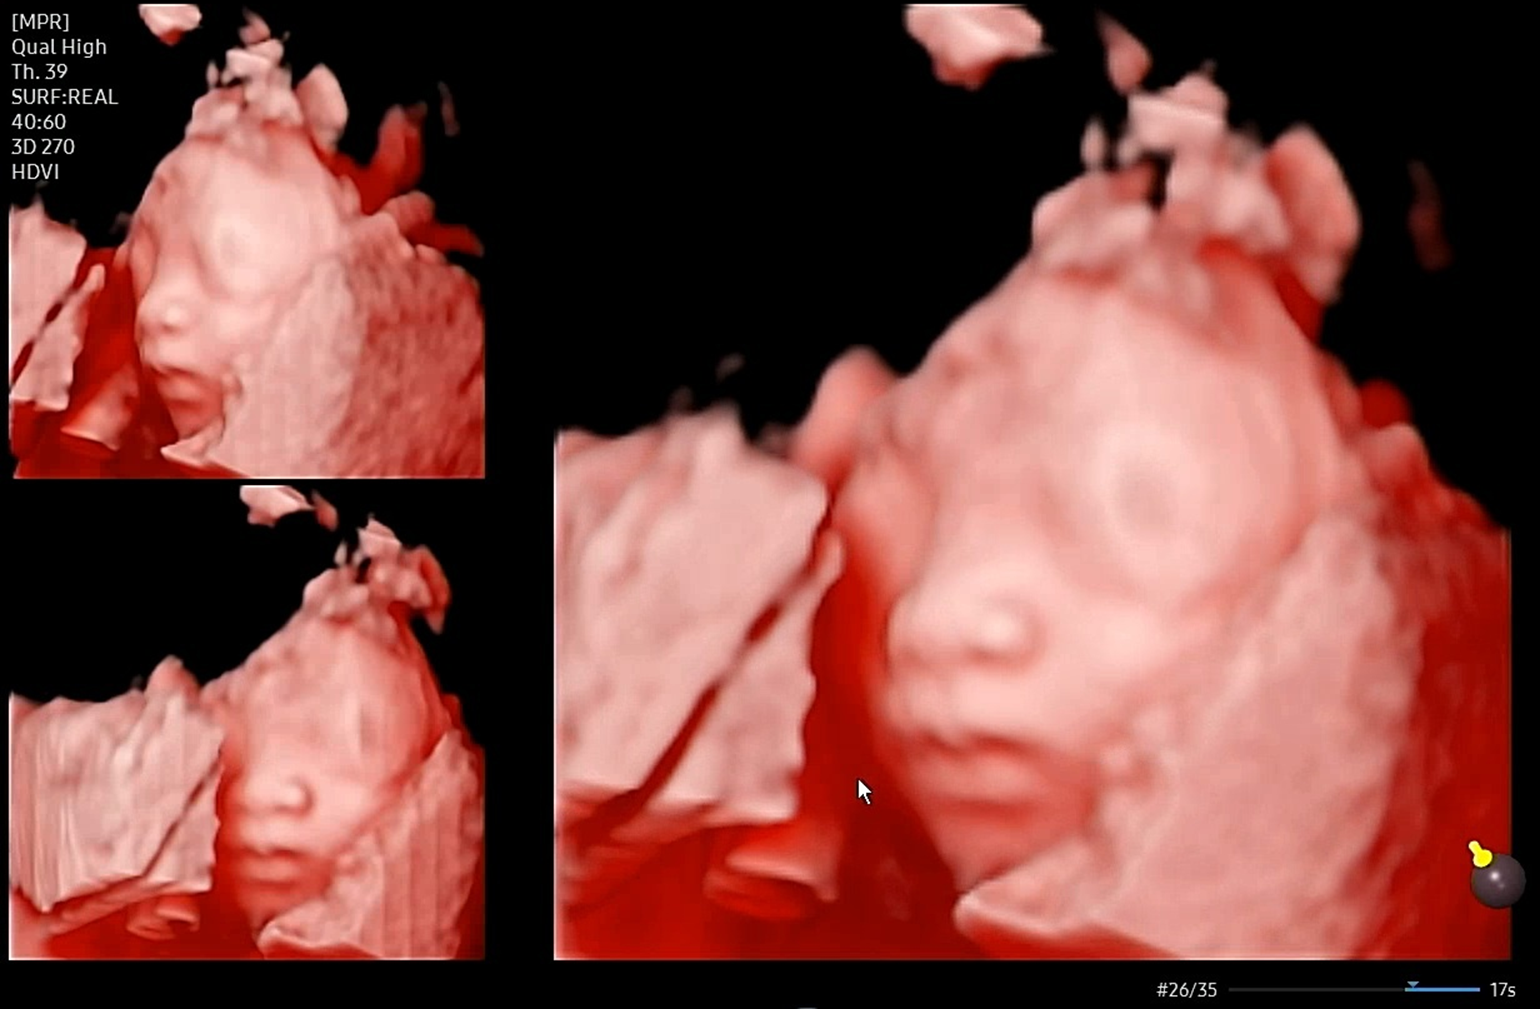

입체 초음파 - 두번째 시도만에 성공!

그 다음주에 바로 입체 초음파 2차 시도!

(입체 초음파도 잘 볼 수 있는 시기가 딱 요맘때라더라. 더 크면 보기 힘들다고..)

초음파 선생님은 더 잘 찍어주려고 계속 노력하시는데 (그래서 40분 동안 봤음..!)

사실 난 이정도면 성공했다고 생각해서

중간에는 더 안 보셔도 될 것 같은데..라는 생각이 들긴 했다 ㅋㅋㅋ

그래도 열정적으로 봐주시니까 좋았다 ㅎㅎ

이 날은 다행히 앞쪽을 보고 있긴 했는데

여전히 계속 얼굴 쪽으로 손을 올려서

손을 내리는 타이밍을 잡는 게 쉽지 않았다.

그래도 아무튼 성공!!

우리 딸 이렇게 생겼구나...! 누굴 닮은 건지 전혀 모르겠다.

정면에서 보면 코가 넙적해서 어라? 했는데

초음파 특성상 원래 좀 퍼져보이는 게 있어서 옆으로 돌려보면 안 그렇다며

초음파실 선생님이 열심히 옆으로도 돌려서 예쁜 사진 나오게 해주셨다 ㅋㅋㅋ